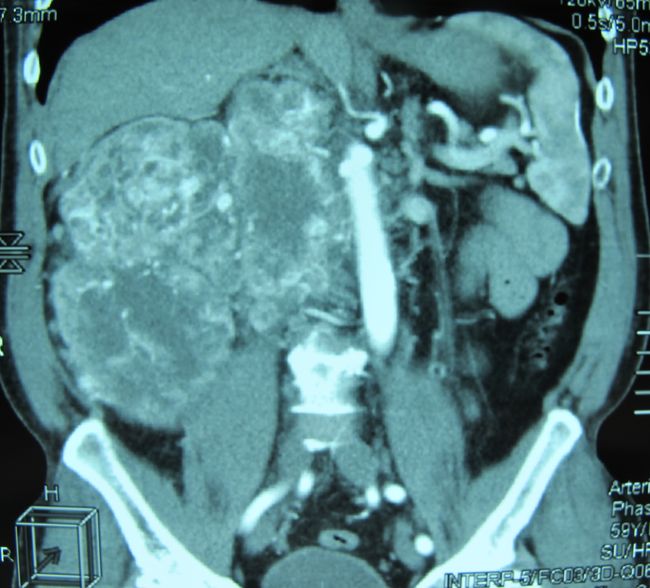

Опухоль правой почки (компьютерная томография)

Опухоль правой почки, сдавливающая нижнюю полую вену